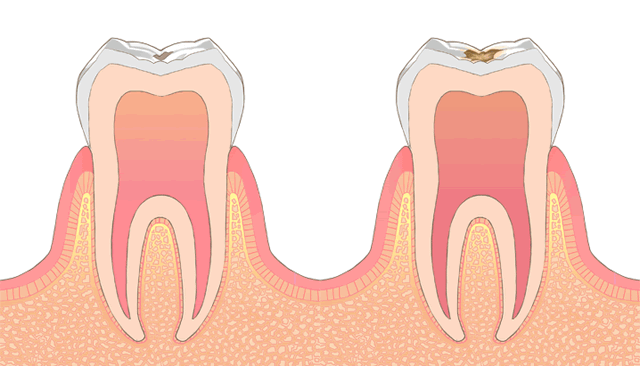

むし歯治療

むし歯とは、むし歯菌が飲食物に含まれている糖を栄養とすることで、あなたの大切な歯を溶かしてしまう病気です。症状は、むし歯の大きさによって異なります。いずれにしても早期発見が大切です。

CO-C1

歯症状もない小さなむし歯であれば、削ることなくブラッシングの技術を向上することで再石灰化を期待し経過観察をします。

C2-C3

小さなむし歯は、詰めものの治療をします。大きなむし歯については、大きさ次第で治療の方針が変わります。詰めるのか被せるのか、根管治療の要不要を判断して考えられる治療方法を丁寧にご説明し同意いただいた上で治療します。